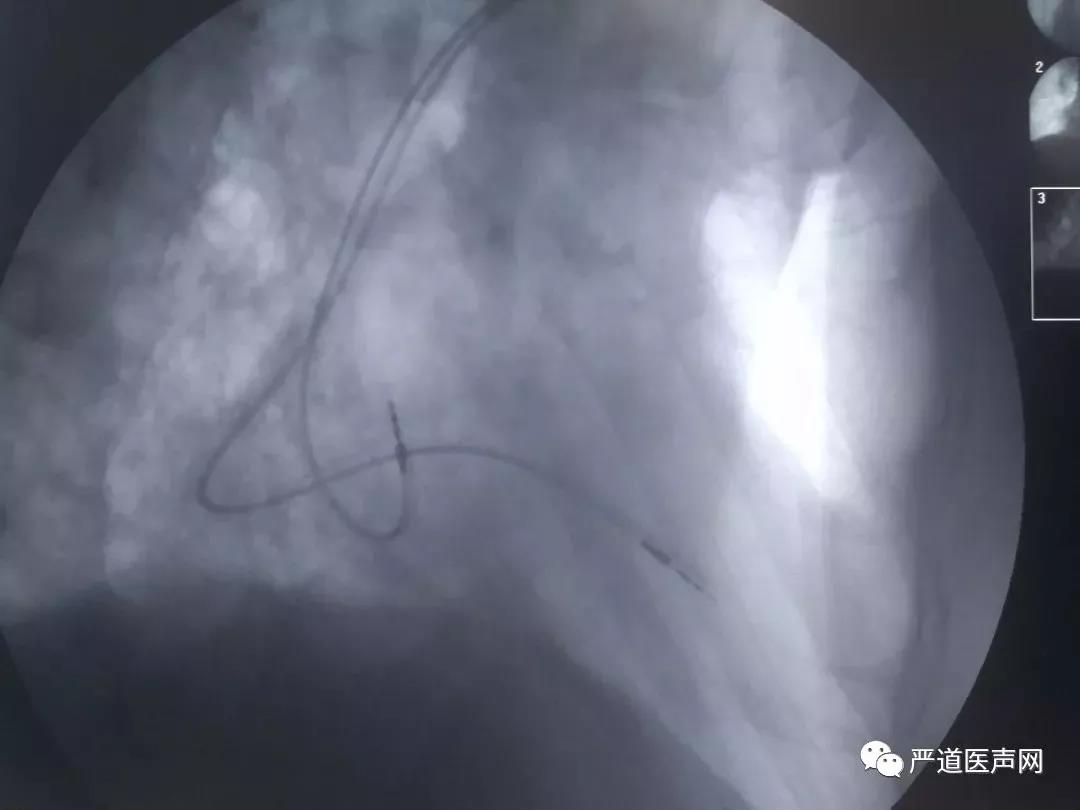

植入后电极位置